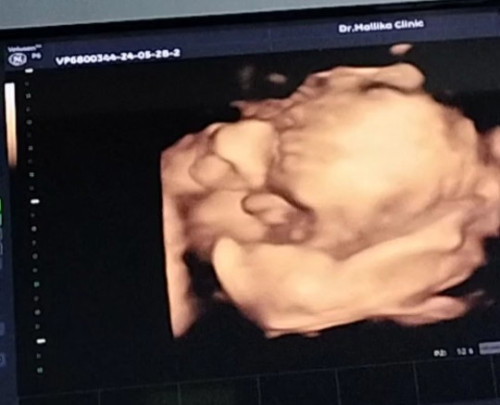

จ๊ะเอ๋ จมูก ปากของหนู มือของหนูปิดหน้าค่ะ